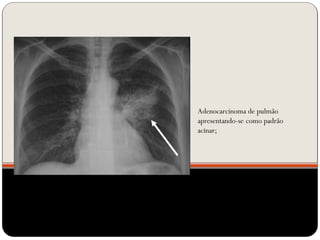

Adenocarcinoma de pulmão

apresentando-se como padrão

acinar;

 O padrão alveolar ou do espaço aéreo é caracterizado por

opacidade homogênea.

 Ocorre pela ocupação do espaço aéreo por outras

substâncias que não o ar: exsudato nas pneumopatias,

transudato nos edemas pulmonares, sangue, células

neoplásicas e materiais estranhos no caso de aspiração (ex.

aspiração de óleo mineral)